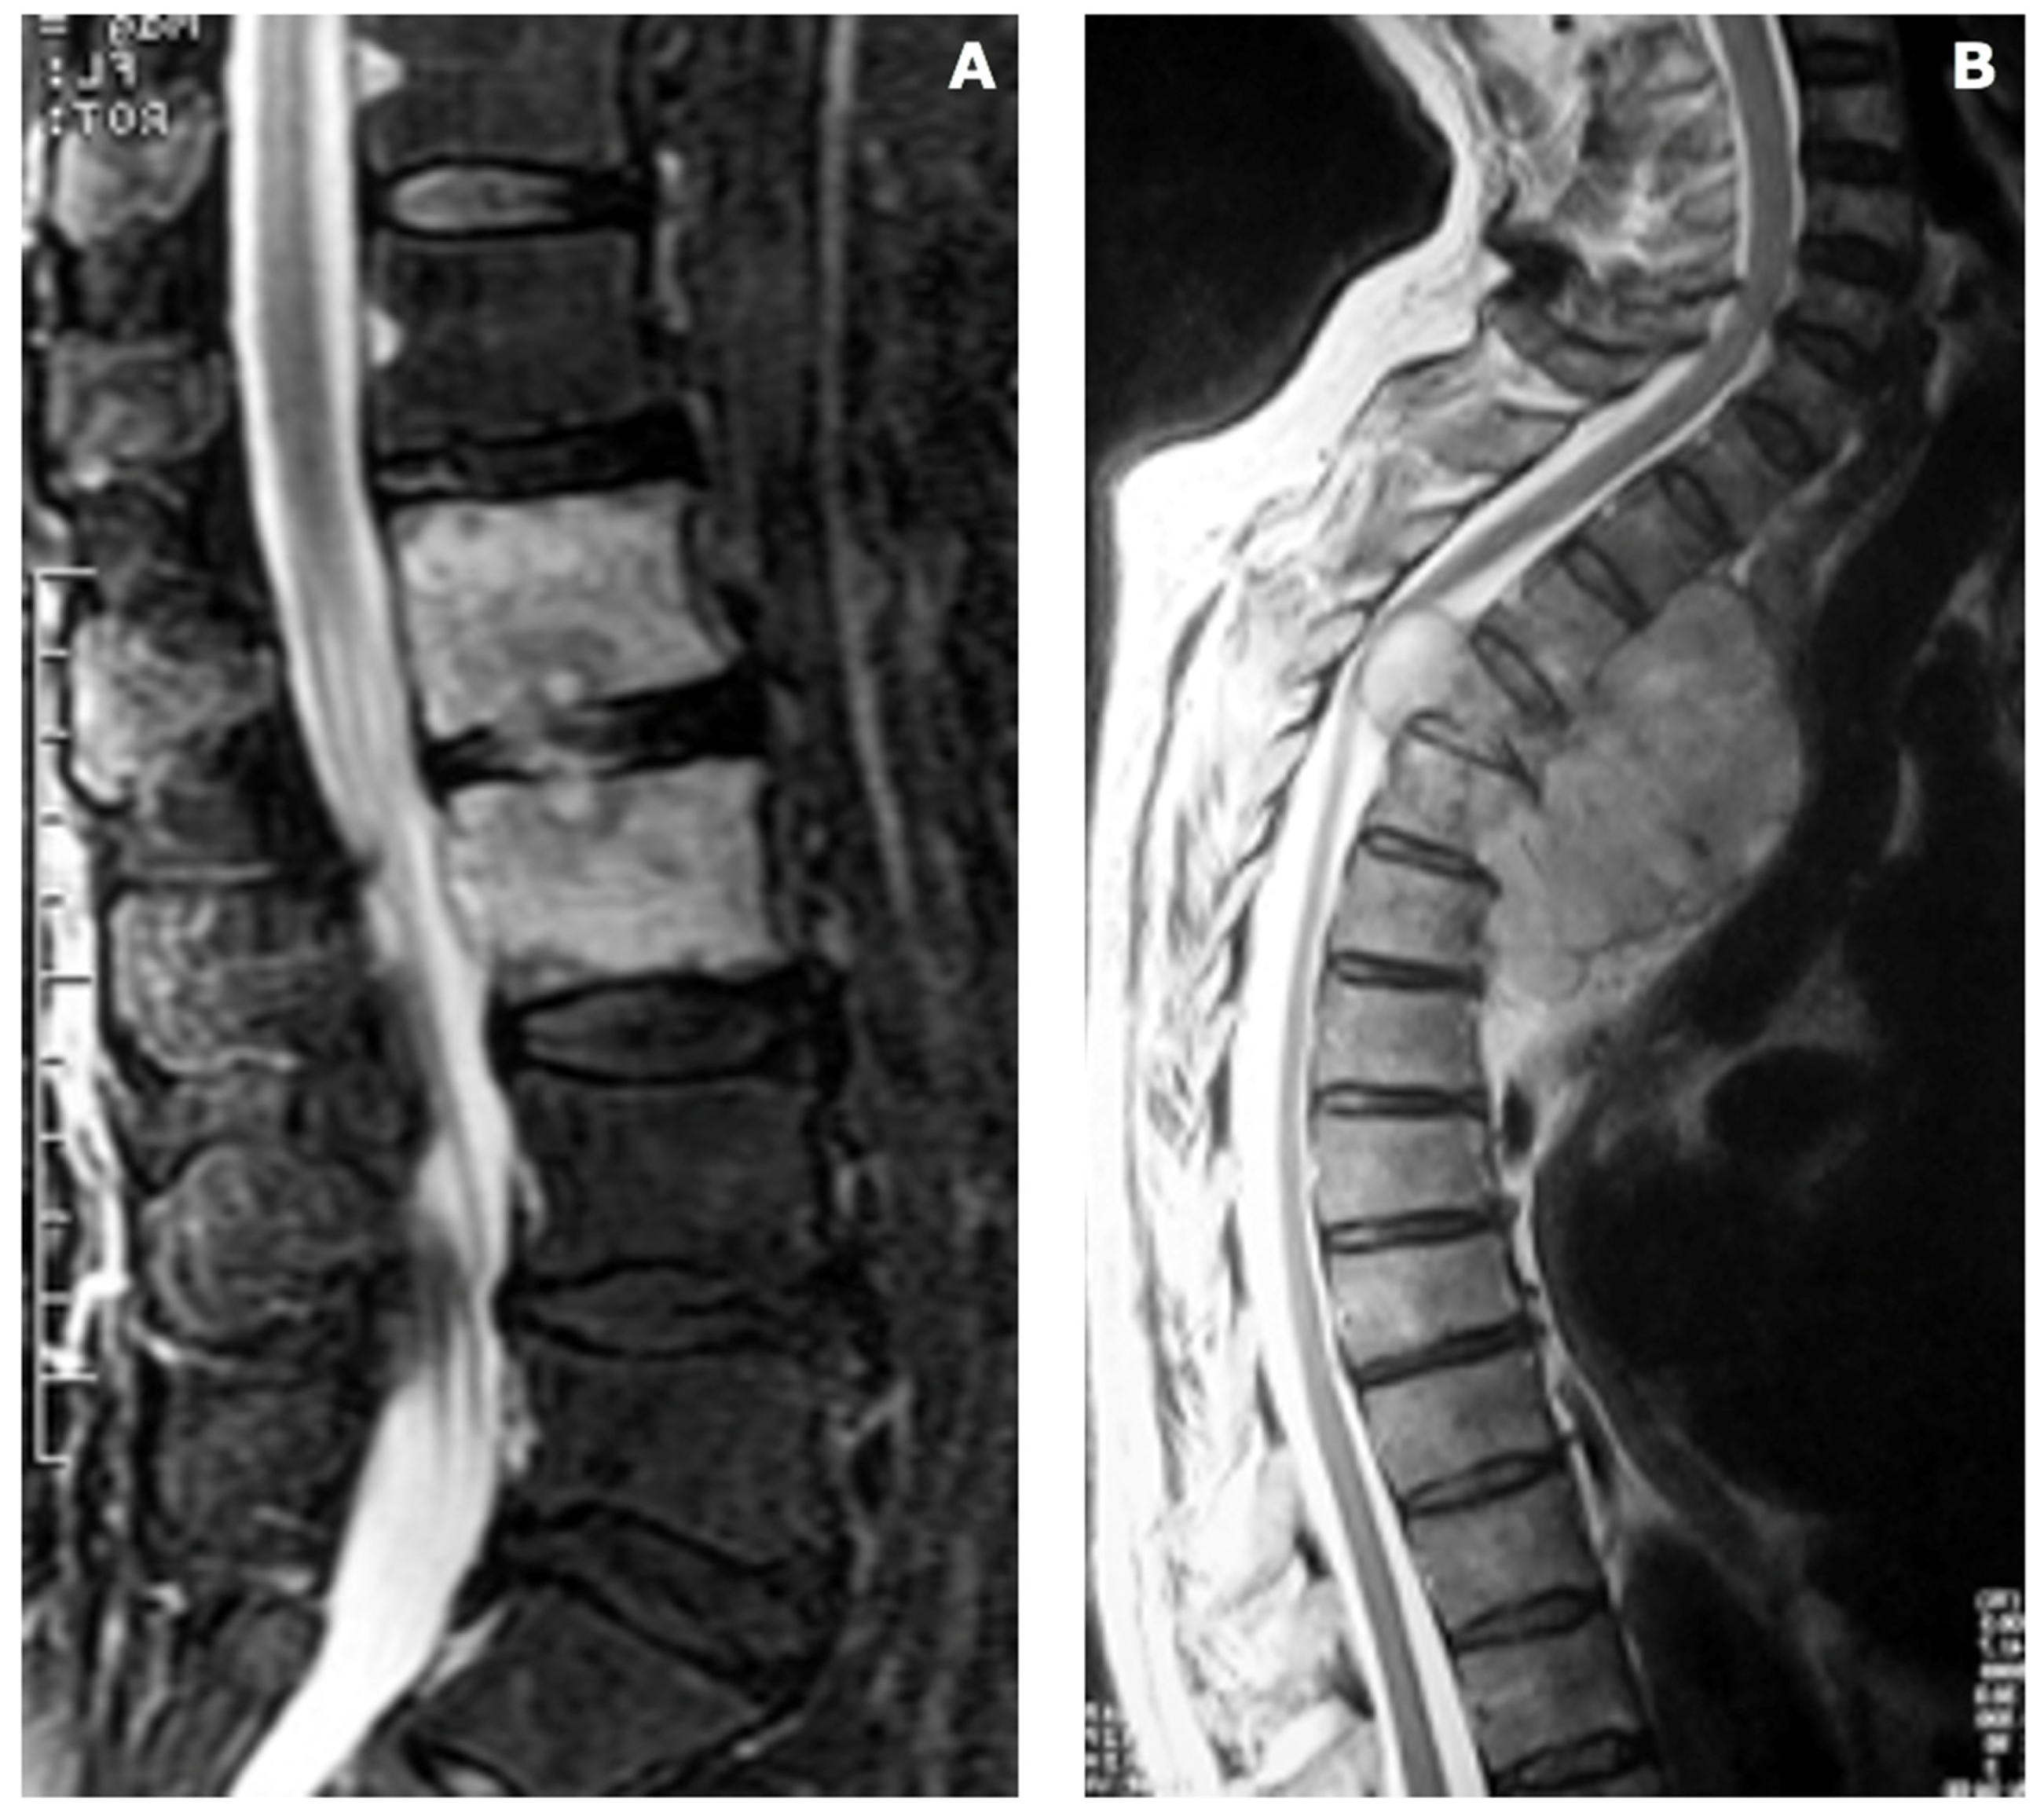

- -

- STAGE 1 => subtle changes, such as increased T2*-weighted signal intensity within the vertebral body, may be evident, indicating marrow edema or inflammation.

- -

- STAGE 2 => T1*-weighted: low signal; T2*-weighted: high signal in the bone marrow and intervertebral disc with heterogeneous enhancement may be observed, reflecting the presence of necrosis, abscess formation or granulation tissue [68,69]; the epidural abscesses show peripheral enhancement with central non-enhancing component.

- -

- STAGE 3 => T1*- and T2*-weighted low signal is due to vertebral collapse and endplate sclerosis.

- Chang, M.C.; Wu, H.T.H.; Lee, C.H.; Liu, C.L.; Chen, T.H. Tuberculous Spondylitis and Pyogenic Spondylitis: Comparative Magnetic Resonance Imaging Features. Spine 2006, 31, 782–788. [Google Scholar] [CrossRef]

- Ledermann, H.P.; Schweitzer, M.E.; Morrison, W.B.; Carrino, J.A. MR Imaging Findings in Spinal Infections: Rules or Myths? Radiology 2003, 228, 506–514. [Google Scholar] [CrossRef]

- Li, Q.; Song, J.; Li, X.; Luo, T.; Peng, J.; Lv, F.; Li, Y.; Huang, Z.; Wang, A. Differentiation of Intraspinal Tuberculosis and Metastatic Cancer Using Magnetic Resonance Imaging. Infect. Drug Resist. 2020, 13, 341–349. [Google Scholar] [CrossRef] [PubMed]

| Spinal Tuberculosis | Cervical and Lumbar spine; A single segment is involved | Collapse and destruction of the vertebra Loss of disc space “Gibbus deformity” Anterior wedging or kyphosis | Erosions, marginal sclerosis, and sequestra formation Lytic lesions Epidural and paraspinal involvement Spinal canal involvement Small bony fragment | relative Blood Flow (rBF) value < 4 relative Blood Volume (rBV) value < 3.5 | Early stage: hypointense on T1-weighted; hyperintense on T2-weighted (marrow edema, inflammation). granulomatous inflammatory response Chronic stage: hypointense on T1-weighted and on T2-weighted images (necrosis, abscess formation) Involvement of adjacent structures (spinal cord, nerve roots, and paraspinal tissues) | Heterogeneous enhancement (necrosis, abscess formation, or granulation tissue) | Early stage: restricted diffusion (low ADC values) Chronic stage: no diffusion restriction with high ADC values | Involvement of vertebral bodies and the related disc with rapid destruction Subligamentous spread with extension into the paraspinal soft tissue with abscesses, usually calcified Extension in epidural space with spinal cord or nerve compression Posterior elements of the vertebra are generally spared |

| Pyogenic Spondylitis | Cervical and Lumbar spine; A single segment is involved | Localized vertebral destruction Loss of disc height Paraspinal soft tissue swelling Bony sequestra, sclerosis, and vertebral collapse | Erosions, sclerosis, and sequestra formation Cortical destruction Sequestration and abscesses | relative Blood Flow (rBF) value < 4 relative Blood Volume (rBV) value < 3.5 | Early stage: hypointense on T1-weighted; hyperintense on T2-weighted (inflammation). granulomatous inflammatory response Chronic stage: hypointense on T1-weighted and on T2-weighted images (necrosis, abscess formation) Involvement of adjacent structures (spinal cord, nerve roots, and paraspinal tissues) | Enhancing inflammatory changes, abscesses, and granulation tissue Ring-enhancing abscesses with peripheral rim enhancement | Early stage: restricted diffusion (low ADC values) Chronic stage: no diffusion restriction with high ADC values | Involvement of vertebral bodies and the related disc with rapid destruction Subligamentous spread with extension into the paraspinal soft tissue with abscesses, usually calcified Extension in epidural space with spinal cord or nerve compression Posterior elements of the vertebra are generally spared |

| Atypical Spinal Tuberculosis | Thoraco-lumbar spine; Multisegmental | Minimal vertebral body involvement Isolated disc space narrowing Abnormal spinal alignment, or signs of instability | Large paravertebral abscesses | Isolated involvement of the posterior elements or a skip lesion pattern Heterogeneous mixed T2-weighted Epidural extension | Involvement of posterior elements Skip lesion separated from each other Extradural spinal cord compression |

| Neoplastic (Primitive) | Mostly Thoracic spine | Vertebral collapse Pathological fractures Abnormal spinal alignment | Destruction, erosion, sclerosis Presence of a bony mass Spinal canal involvement Erosion of the cortical bone Presence of spinal cord compression or nerve root impingement | relative Blood Flow (rBF) value > 4 relative Blood Volume (rBV) value > 3.5 | Location, size, extension Extent of spinal cord compression, evaluate nerve root involvement, and identify the presence of cystic or necrotic components within the tumor Various imaging features on MRI | Intense contrast enhancement in homogeneous or ring-like enhancement | Restricted diffusion (low ADC values) | Vertebral body and posterior elements involvement Preserved disc Halo Sign |

| Neoplastic (Metastasis) | Mostly Thoracic spine | Osteolytic, osteoblastic, or mixed lytic/blastic lesions Destructive bone lesions Loss of vertebral body height Pathologic fractures | Destruction, cortical thinning A soft tissue mass | relative Blood Flow (rBF) value > 4 relative Blood Volume (rBV) value > 3.5 | Location, size, extension Extent of spinal cord compression, evaluate nerve root involvement, and identify the presence of cystic or necrotic components within the tumor Various imaging features on MRI | Homogeneity, heterogeneity, or rim enhancement, can provide insights into the aggressiveness and vascularity of the metastatic lesions | Restricted diffusion (low ADC values) | Vertebral body and posterior elements involvement Preserved disc |